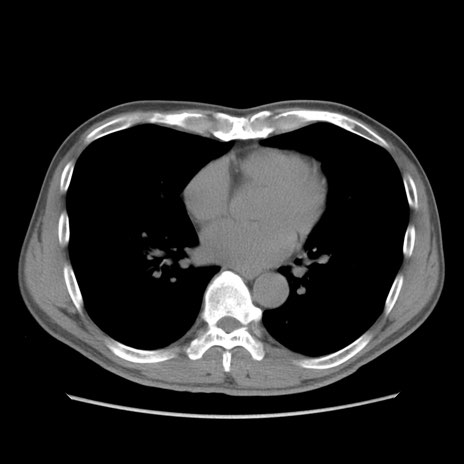

症例56 CT(横断像)

脂肪ウインドウ